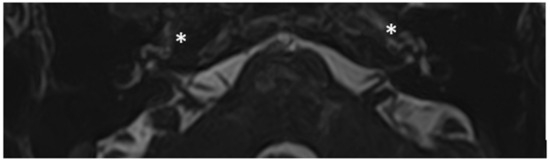

Within a few years, both ears showed a worsening of bone threshold to SNHL bilaterally. In 2017 (27 years since diagnosis) she developed profound SNHL with left-sided anacusis and underwent cochlear implantation in the left ear. CT and MR images showed a large cavity around the basal turn of the cochlea and massive osteorarefaction around the cochlea (‘double ring’ sign). The cavity appeared to contain cerebrospinal fluid but did not communicate with the cochlear lumen (Figure 1 and Figure 2).

Figure 1. CT images of patient #1 with osteogenesis Imperfecta. (A,B), right side in axial plane. (C,D), right side in coronal plane. (E,F), left side in axial plane. (G,H), left side in coronal plane. A pericochlear cavity is visible in all figures; arrows indicate its origin from the IAC. Asterisks indicate extension of osteorarefation into the cochlea.

Figure 2. MR image of patient #1 with osteogenesis Imperfecta. MR cisternography showing the fluid-signal in the newly formed cavity (white asterisk).